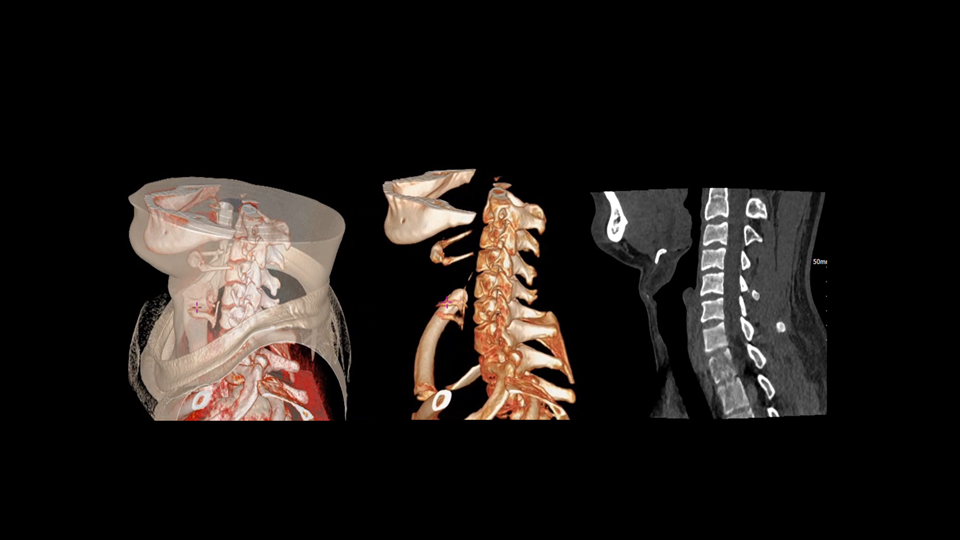

去金属伪影,影像更纯净

uCT SiriuX® 提供系统化金属伪影抑制解决方案。能谱扫描结合 PureBeam 纯光滤能技术,从源头有效减少硬化伪影;DeepMAC深度学习金属伪影校正算法针对射线饥饿、散射等多种成因进行优化重建,从物理与算法双层面显著提升金属植入区域的图像质量与可诊断性。

高能级虚拟单能成像

双宽能谱成像提供高能级虚拟单能图像,结合硬化伪影校正技术,有效提升金属与组织对比度,源头抑制金属物质类硬化伪影。

PureBeam纯光滤能技术

球管端采用锡材质滤过,有效滤过低能光子,提升能谱扫描的高低能分离度,减少能量重叠。

DeepMAC深度学习金属伪影校正算法

基于深度学习网络模型,应对髋关节置换体、脊柱内固定器、四肢骨科植入物、牙科修复体以及血管介入弹簧圈等各类金属植入物伪影,还原清晰解剖结构。